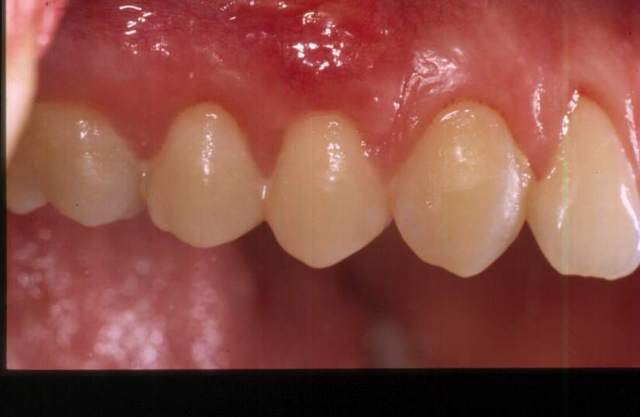

et la suite.

J'aime bien tes sutures, elles m'ont l'air bien étanches.

Et quel sens artistique, le blanc se détache vraiment bien sur le rouge sang.